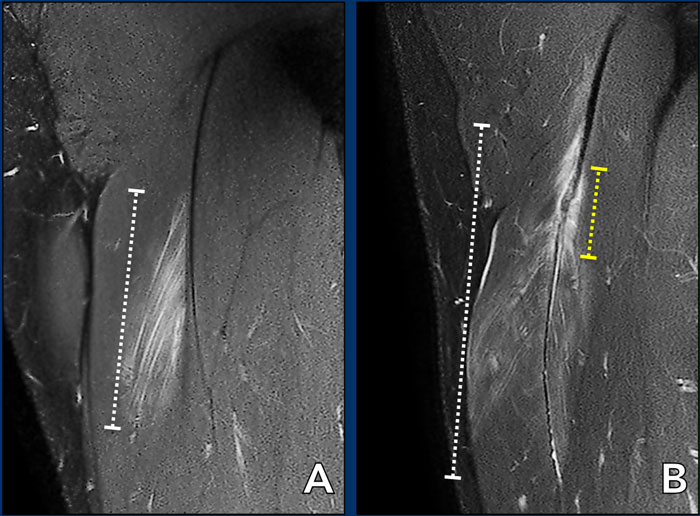

La differenza tra la lesione b e c riguarda praticamente l'aspetto della giunzione miotendinea. Se la giunzione risulta interessata da edema senza distorsione/ondulazione rientra nel tipo b. Qualsiasi modificazione dell'aspetto morfologico della giunzione rientra naltresì nel tipo c. Vedi esempio sottostante. Fig a sinistra tipo b, figura a destra tipo c.